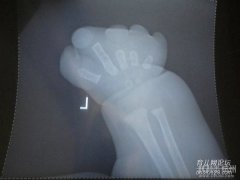

杭州艾玛妇产医院生产后 发现有纱布留在体内 简直是够毒辣

据一些网民朋友揭发称:上周一产妇在杭州艾玛妇产医院生产后,发现有纱布留在体内。患者家属质疑是由于医院医护人员工作不仔细导致...

杭州艾玛妇产医院够猥琐!生产后纱布留在体内